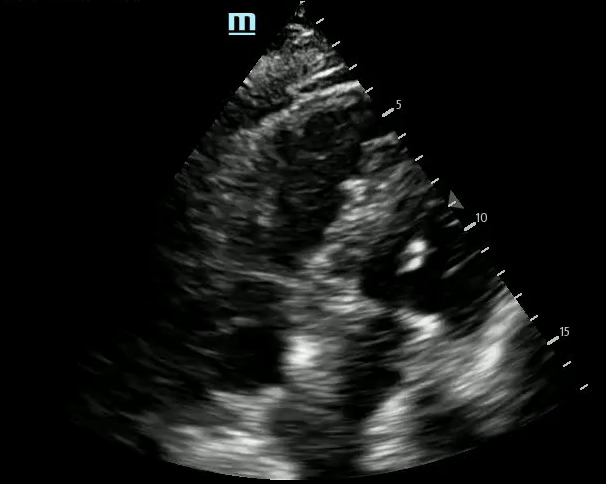

Images – Echocardiography

Pericardial and Pleural Effusions

Pericardial Effusion

Pacer Lead Migration

Mitral Valve Prolapse

Left Atrial Mass

Complete Heart Block

Atrial Flutter

Supine vs Left Lateral Decubitus

Normal 4 View Echo